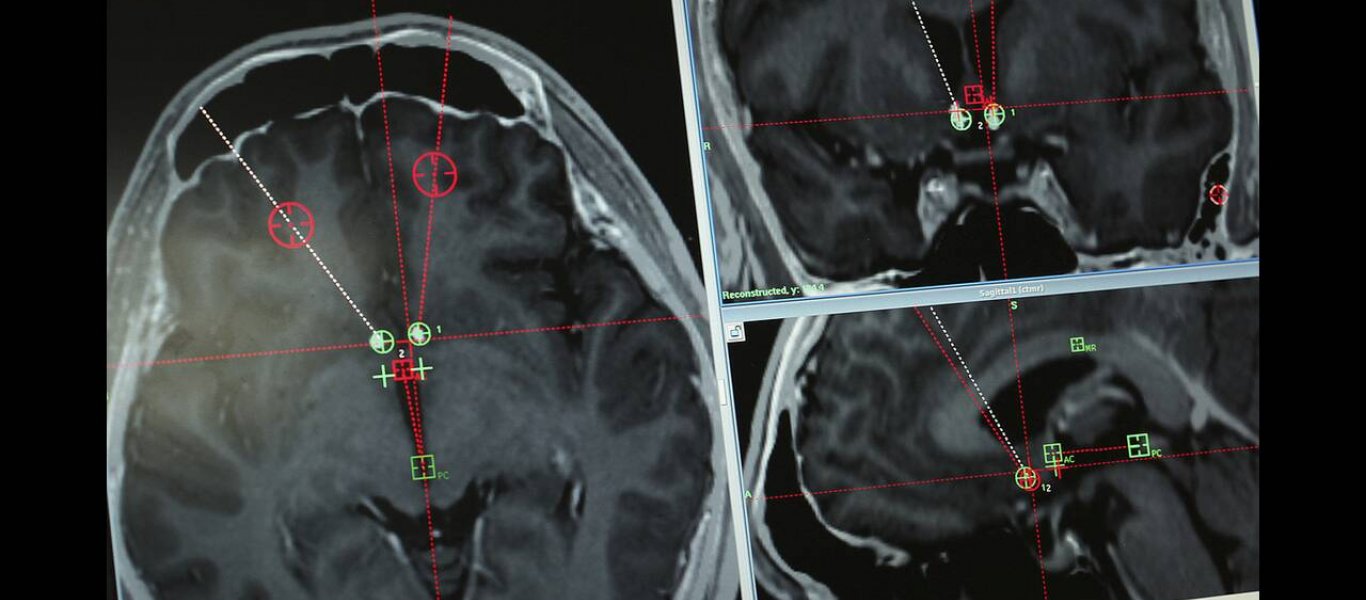

Η επέμβαση έγινε σε νοσοκομείο της Σανγκάης στην Κίνα και είναι η πρώτη φορά που γίνεται κλινική δοκιμή της μεθόδου που στοχεύει στο να βοηθήσει τους χρήστες μέσω «βαθιάς εγκεφαλικής διέγερσης».

Οι επιστήμονες, όπως αναφέρει η Sun, τοποθέτησαν σε ειδικό σημείο του εγκεφάλου μία συσκευή που μοιάζει με βηματοδότη και προκαλεί ηλεκτρικές διεγέρσεις σε επιθυμητά μέρη του.

Η μέθοδος της βαθιάς διέγερσης του εγκεφάλου είναι μία θεραπεία που χρησιμοποιείται εδώ και μεγάλο διάστημα σε ασθενείς με κινητικά προβλήματα, πλέον όμως ρίχνεται δυναμικά και στον πόλεμο κατά των οπιοειδών.